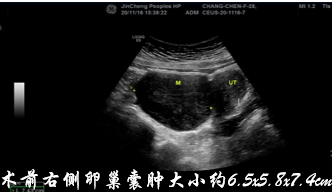

除了甲状腺囊肿,以下囊肿也适用微创硬化术: